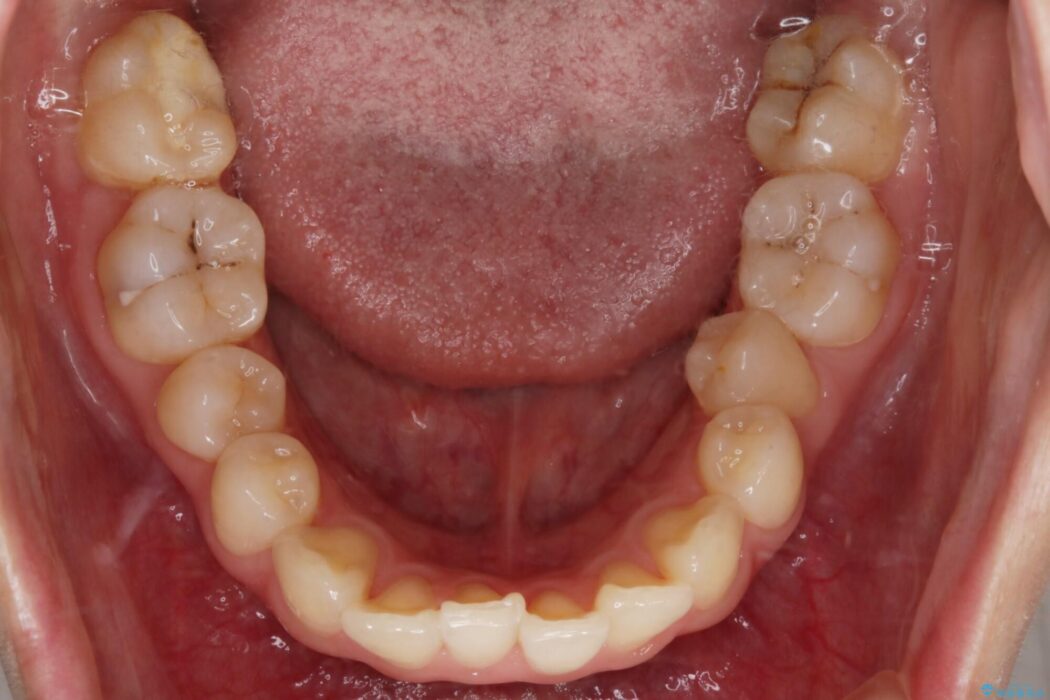

【20代女性】ブライダルに向けた矯正できれいなスマイルラインへ

- 患者様:20代女性

- 治療期間:1年10ヶ月

- 矯正装置:インビザライン コンプリヘンシブパッケージ

笑った時に見える歯並びをきれいにしたいとの主訴で来院されました。

ガタつきの度合いから抜歯は不要と判断しましたので、マイクロインプラントを用いて歯全体を遠心移動させていくことでねじれや噛み合わせのズレを改善していく計画を立てました。